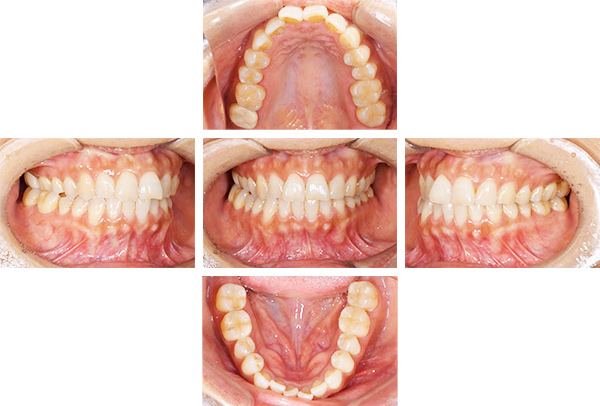

インレー症例

治療前

治療後

治療期間 4回(1ヶ月)

費用 セラミックインレー8本

合計:440,000円

治療リスク・副作用 ・詰め物、被せ物をする時は自分の歯を削ることになります

・歯ぎしり・食いしばりが強い方は、セラミックが割れてしまうことがあります。

費用 ・セラミックインレー5本

合計:275,000円